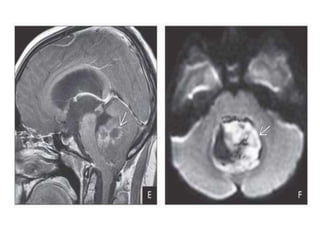

Sagittal T1 C+ scan of a PTPR shows an enhancing pineal mass causing

obstructive hydrocephalus.

Imaging findings are nonspecific

Sagittal T1 C+scan of a PTPR shows an enhancing pineal mass causing obstructive hydrocephalus. Imaging findings are nonspecific

gland calcifications. Sagittal T1WI in the same patient shows a well-defined pineal

mass compressing the tectal plate inferiorly , causing severe obstructive

hydrocephalus

Post-ventriculostomy NECT scanshows hyperdense pineal mass “engulfing” pineal gland calcifications. Sagittal T1WI in the same patient shows a well-defined pineal mass compressing the tectal plate inferiorly , causing severe obstructive hydrocephalus